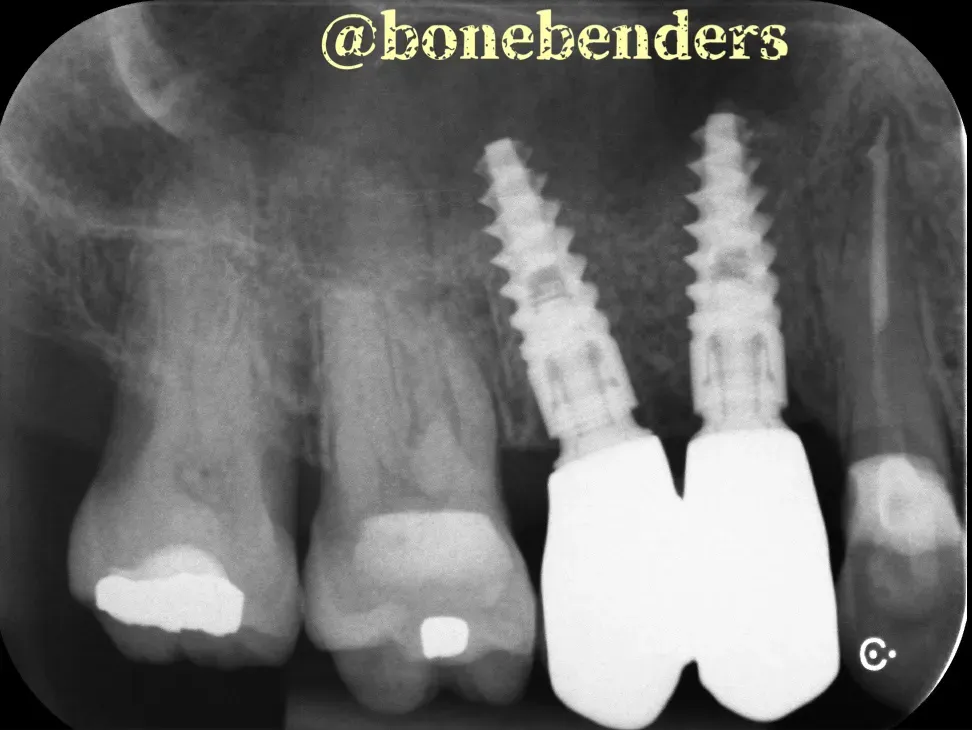

Le immagini sottostanti mostrano i risultati clinici e radiografici della procedura. Gli impianti sono due Newton di Kalodon 3.8x13 mm. È chiaro che l’espansione ossea è tridimensionale e che anche il volume del tessuto cheratinizzato è notevolmente aumentato.

Pensaci: tutto questo è stato realizzato naturalmente, senza innesti. I tempi di guarigione sono identici a quelli delle procedure osteotomiche classiche. Non c’è bisogno di aspettare periodi più lunghi, cosa necessaria, al contrario, con GBR e i sollevamenti laterali del seno. È davvero sorprendente ciò che possiamo ottenere con le tecniche di “bonebending”.

Come vedi, l’osteointegrazione è perfetta e il risultato estetico eccellente. Tutto questo senza biomateriali, senza membrane, senza complicazioni. Solo la potenza della biologia naturale guidata da tecniche precise.